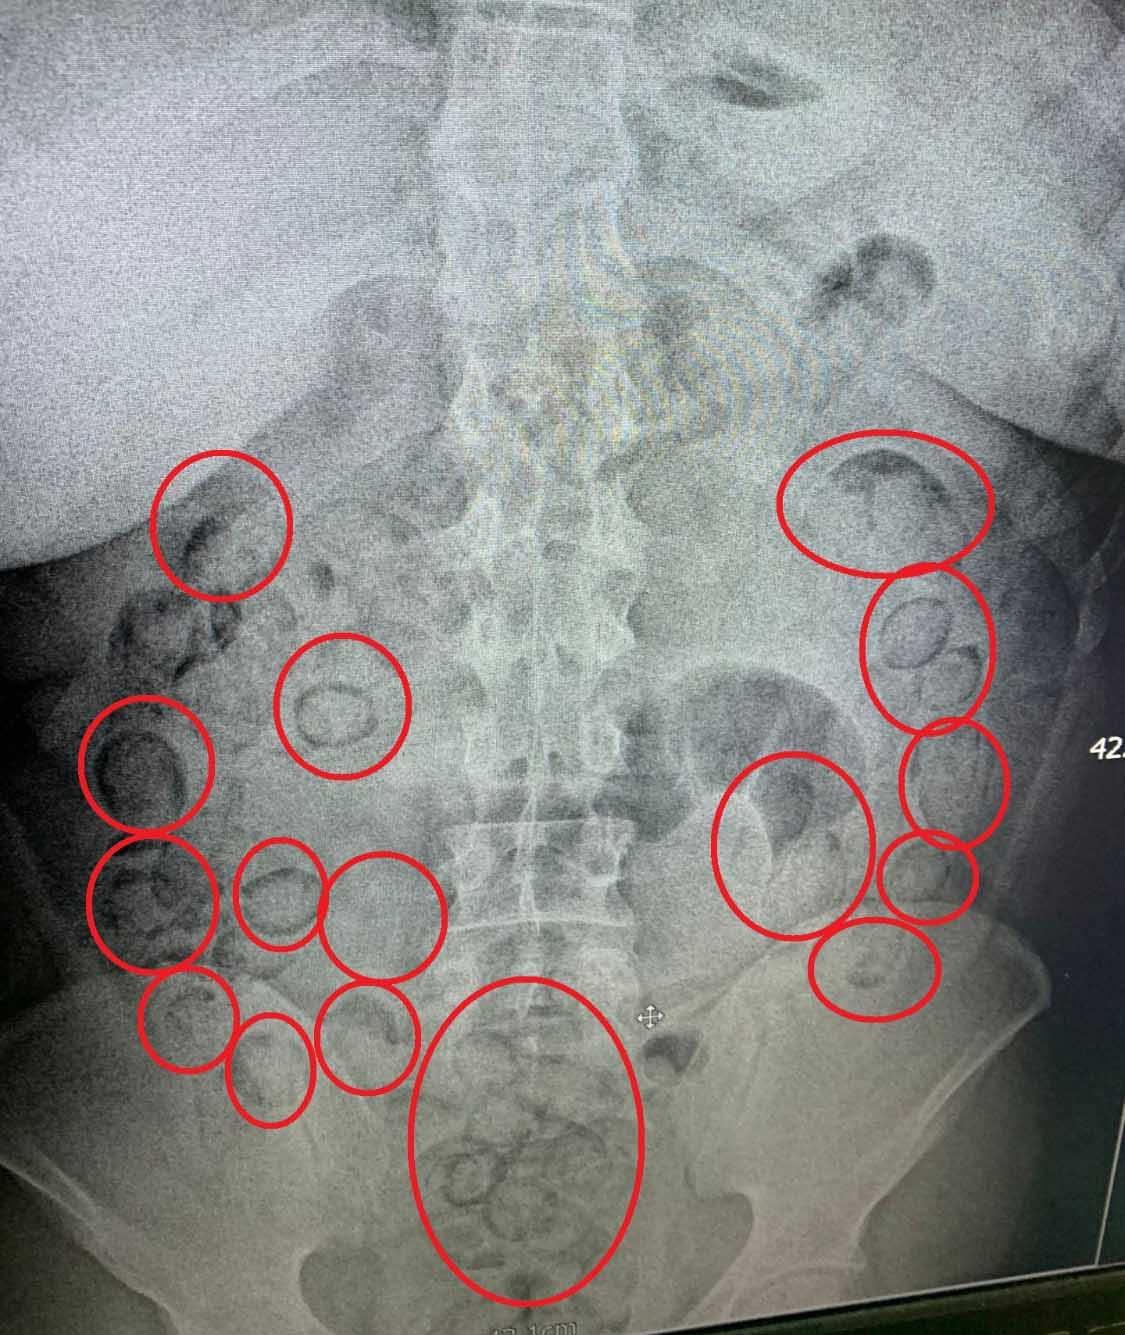

Aksaray Eğitim ve Araştırma Hastanesi’ne götürülen A.M.'nin çekilen röntgeninde midesinde uyuşturucu tespit edildi. Tıbbi müdahale ile A.M.’nin midesinden 101 parça halinde 433 gram metamfetamin çıkarıldı.